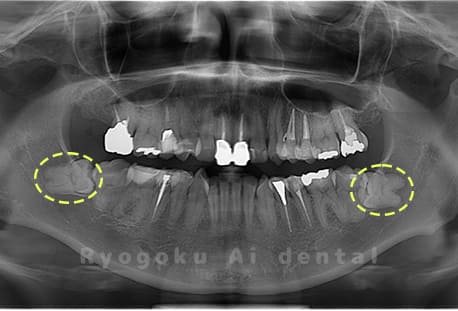

Case02

-

- 原因

- 下顎の水平埋伏智歯

- 治療内容

- 下顎の水平埋伏智歯を抜歯

<リスク・副作用>

手術後は痛み、腫れ、痺れなどの副作用が生じる場合があります。